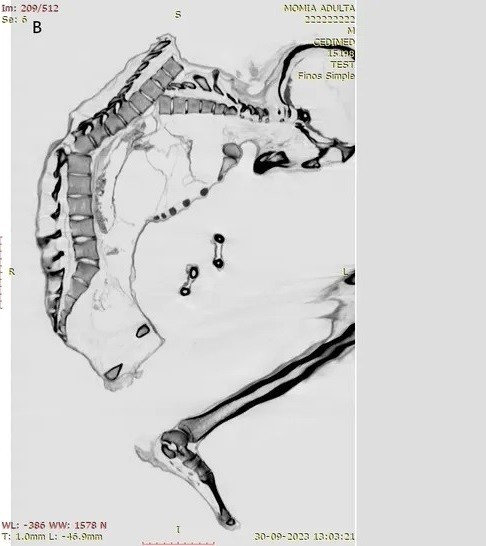

Trên xác ướp có nhiều bằng chứng về chấn thương do lực tác động mạnh cho thấy người đàn ông có thể đã thiệt mạng do đá lở hoặc sập hầm mỏ. Trong nghiên cứu mới công bố, các chuyên gia đã chụp CT và chụp X-quang để giải mã chi tiết những chấn thương nghiêm trọng có thể đã dẫn đến cái chết của người đàn ông trên. Ảnh: Francisco Garrido and Catalina Morales.

Nhiều vết nứt chưa lành được phát hiện trên phần cột sống trên của người đàn ông. Người này cũng bị gãy xương sườn, xương bả vai và xương đòn, cho thấy "một lực tác động mạnh lên một vùng rộng" ở phần lưng trên, tiết lộ rằng "phần ngực trên bên trái của ông chịu lực tác động chính". Điều này đã dẫn tới một số đốt sống bị lệch và làm xẹp lồng ngực. Ảnh: geologyin.com.

Ngoài ra, các nhà nghiên cứu đã xác định được một vết nứt ở đốt sống gần gốc cột sống của thợ mỏ, có khả năng là hậu quả của chấn thương ban đầu ở phần lưng trên. Cả chấn thương cột sống trên và dưới đều "thường liên quan đến tổn thương tủy sống nghiêm trọng và tỷ lệ tử vong cao. Ảnh: pueblodirect.com.

Nhóm nghiên cứu không phát hiện thấy thương tích nào ở hộp sọ, cổ hoặc cánh tay của người đàn ông. Điều này cho thấy vụ tai nạn xảy ra khi người thợ mỏ đang ở tư thế cúi đầu. Lúc xảy ra tai nạn lao động, có thể ông đang tập trung khai thác ngọc lam hoặc có lẽ đang cố gắng bảo vệ phần đầu bằng hai tay khi một tảng đá nặng rơi từ trên cao rơi xuống. Ảnh: pueblodirect.com.